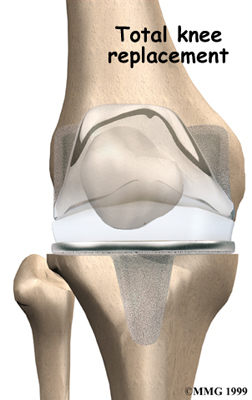

Artificial Knee Replacement

An artificial knee replacement is the ultimate solution for advanced knee OA.

Surgeons prefer not to put a new knee joint in patients younger than 60. This is because younger patients are generally more active and might put too much stress on the joint, causing it to loosen or even crack. A revision surgery to replace a damaged prosthesis is harder to do, has more possible complications, and is usually less successful than a first-time joint replacement surgery.

Related Document: Fyzical Bolingbrook's Guide to Artificial Joint Replacement of the Knee